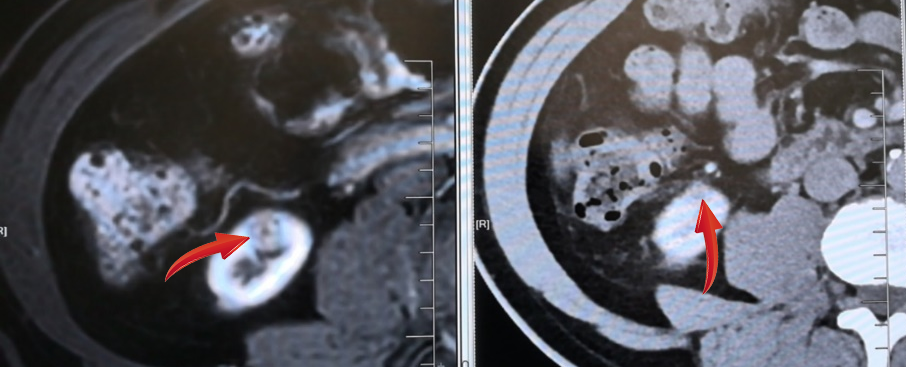

近期,55岁的王女士,因“胃脘胀痛半年” 入院,本来打算看个胃病,结果火眼金睛的放射科医生在其腹部增强CT中看出“端倪”:右肾下极占位(弱强化灶),大小:9.5mm,考虑MT可能,遂立即转入泌尿外科,排除手术禁忌证后在全麻下行“腹腔镜下肾部分切除术”,手术顺利,术后恢复良好。病理显示:透明细胞性肾细胞癌。

无独有偶,62岁的金先生,在放射科诊查泌尿系平扫+增强CT+CTU中:患者右肾上极肿块,囊实性,包膜完整,直径约1.5cm肿瘤,与周围少粘连;入院后完善术前检查,排除手术禁忌证后在全麻下行“腹腔镜下肾部分切除术”,手术顺利,术后恢复良好。病理显示:透明细胞性肾细胞癌。

由于显影、诊断能力等各项不确定因素的存在,通常肿瘤在3cm以下很容易被漏诊,这次9.5mm肿瘤被探查出,放射科医生火眼金睛的背后是专业、细心和责任!